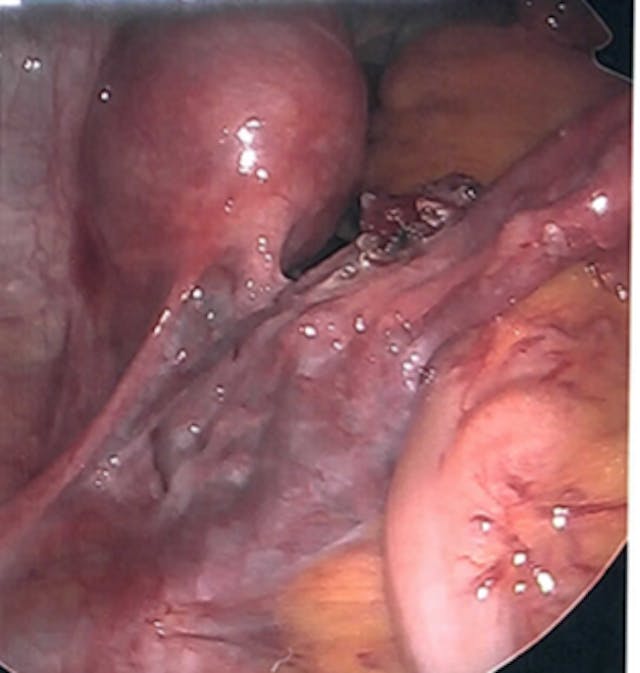

With my ectopic pregnancy, I encountered my preborn baby’s humanity in a new way. The surgeon was able to take pictures throughout the laparoscopic procedure, and he sent me home with these photos when I was discharged from the hospital.

When I finally felt ready to look at these photos a few weeks later, I saw it all — the distended Fallopian tube, the gestational sac. And then, a sight that took my breath away.

I saw my baby.

She had a head, eyes, little nubs for arms and legs, just like I had seen on the ultrasound of my 6-week twins a few years before… but this was a photo. I was overwhelmed by emotion, but also completely clear on one thing: that is my child.

We named our baby Renee, which means “reborn.” She was never able to be born on this earth, but we know with certainty that she is in the arms of Christ her Creator. In her photo, she is perfect. She is beautiful. She is fully and unquestionably human. Through no fault of her own, she was in the wrong place and could not be saved, much to our grief. May her short life and the stunning photos of her humanity be used to change hearts.